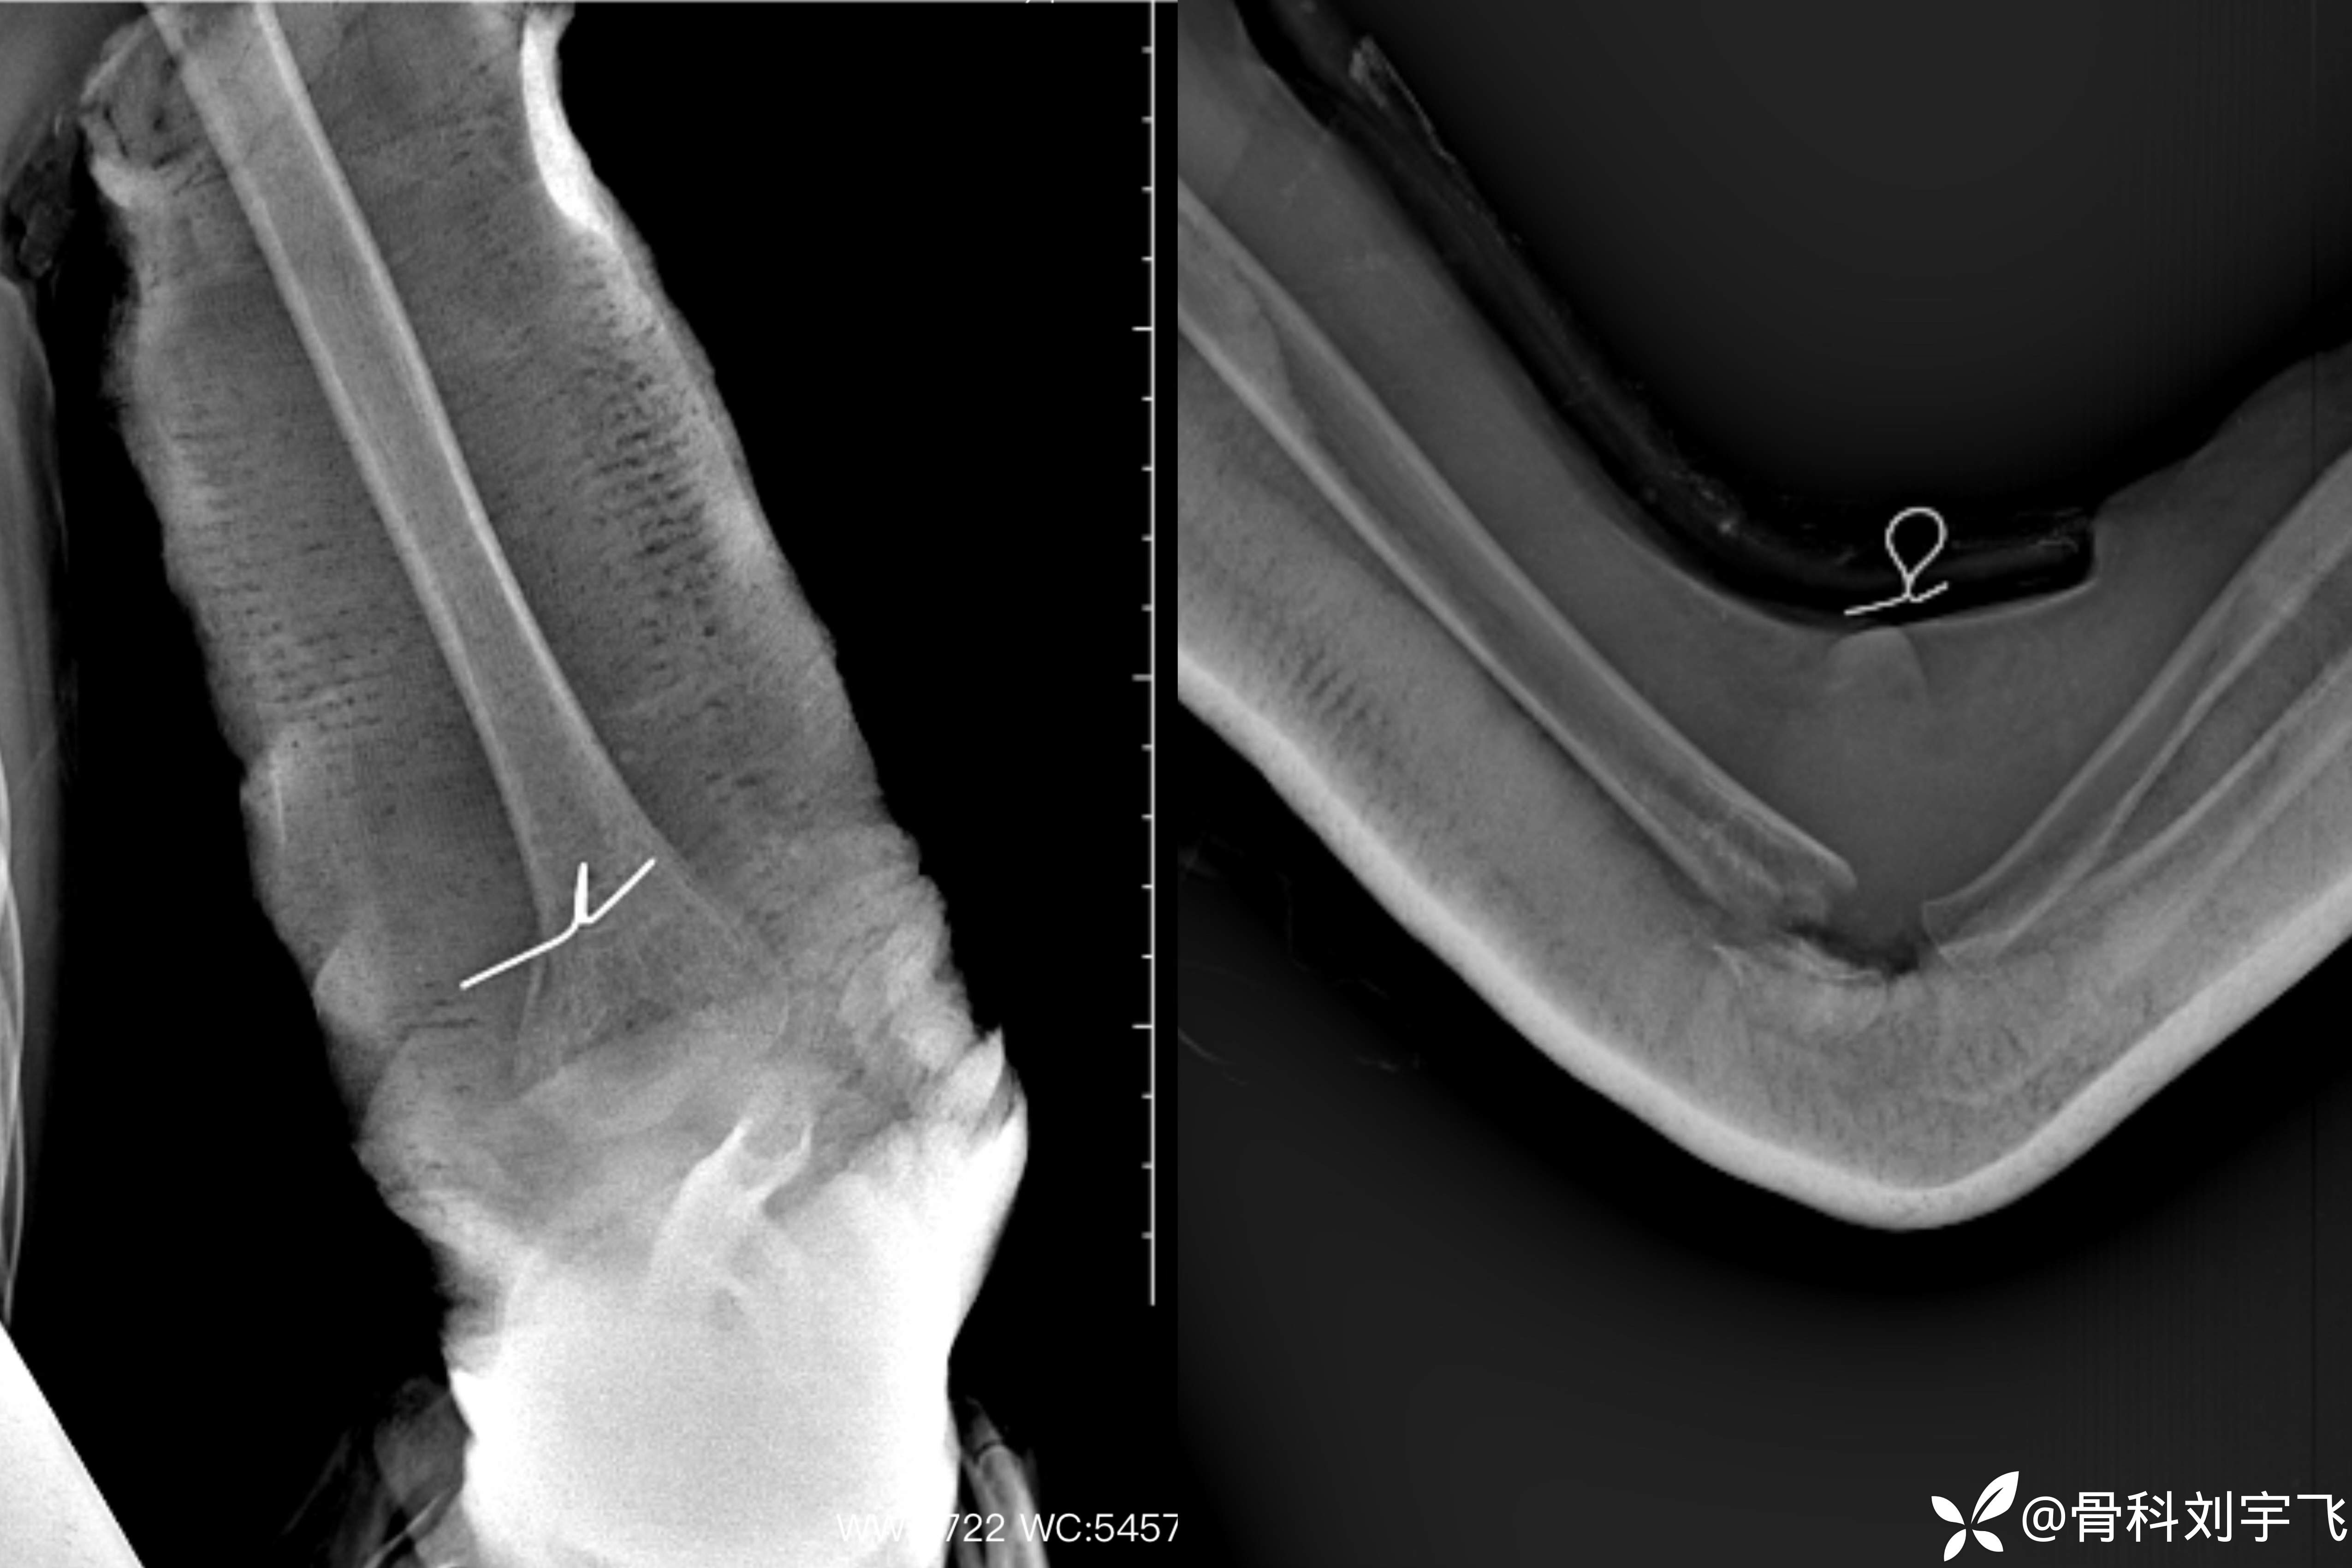

首次复位后:

正位尺偏移位恢复,侧位骨折端仍有旋转,石膏固定,择期调整。

三周后复查:正位及侧位骨折端位置力线良好给予小夹板固定。